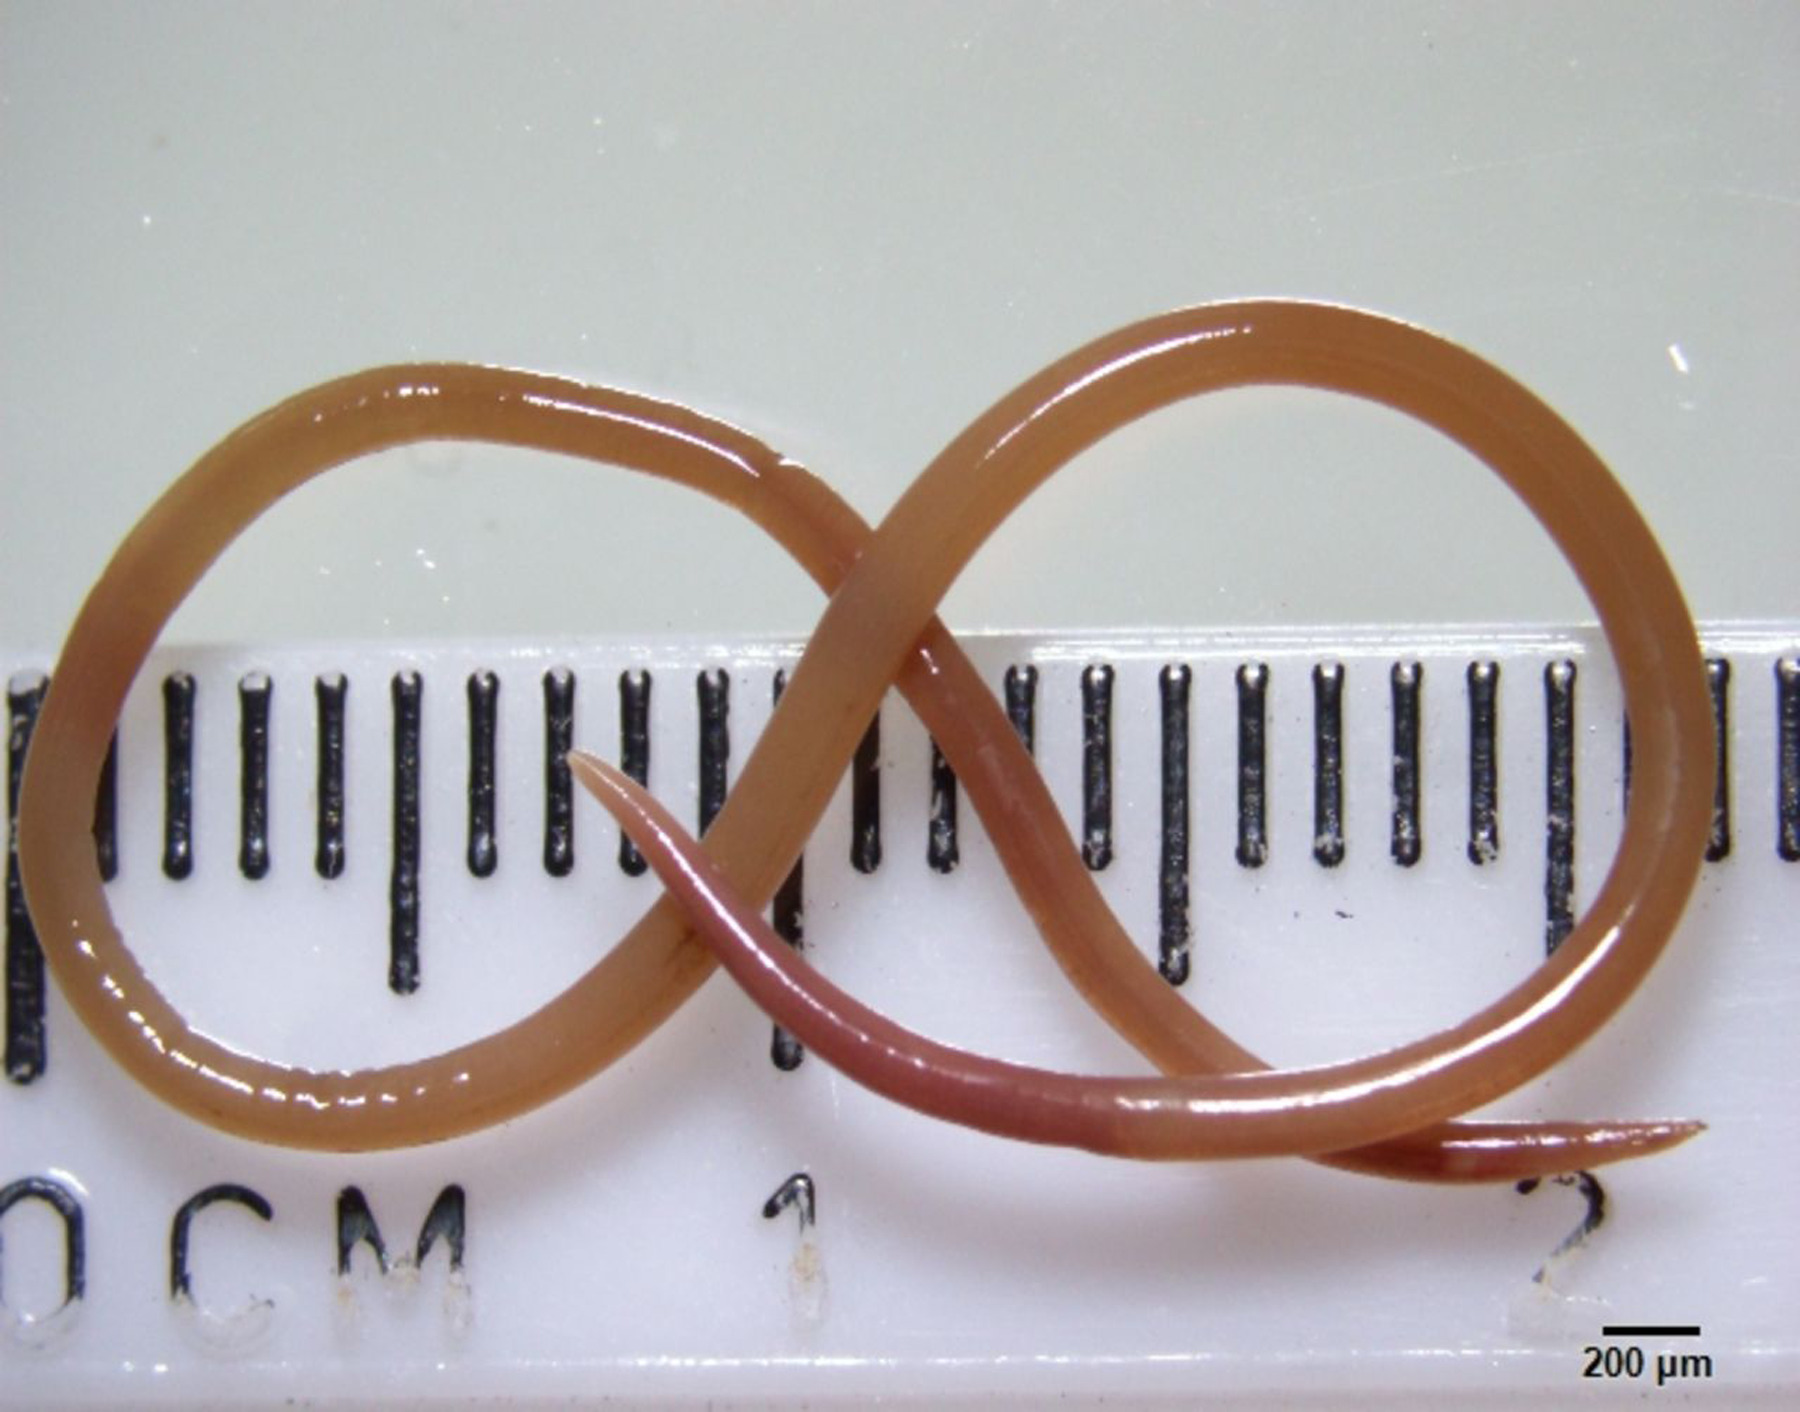

«Η Καμπέρα είναι ένα μικρό μέρος, οπότε στείλαμε το σκουλήκι, το οποίο ήταν ακόμη ζωντανό, κατευθείαν στο εργαστήριο ενός επιστήμονα του CSIRO, ο οποίος έχει μεγάλη εμπειρία με τα παράσιτα», σημείωσε ο Senanayake και συμπλήρωσε «απλώς το κοίταξε και είπε: ‘Θεέ μου, αυτό είναι το Ophidascaris robertsi’».

Το Ophidascaris robertsi είναι ένα στρογγυλό σκουλήκι που συναντάται συνήθως στους πύθωνες και η ασθενής του νοσοκομείου της Καμπέρα είναι η πρώτη περίπτωση παγκοσμίως που το παράσιτο βρέθηκε σε άνθρωπο.